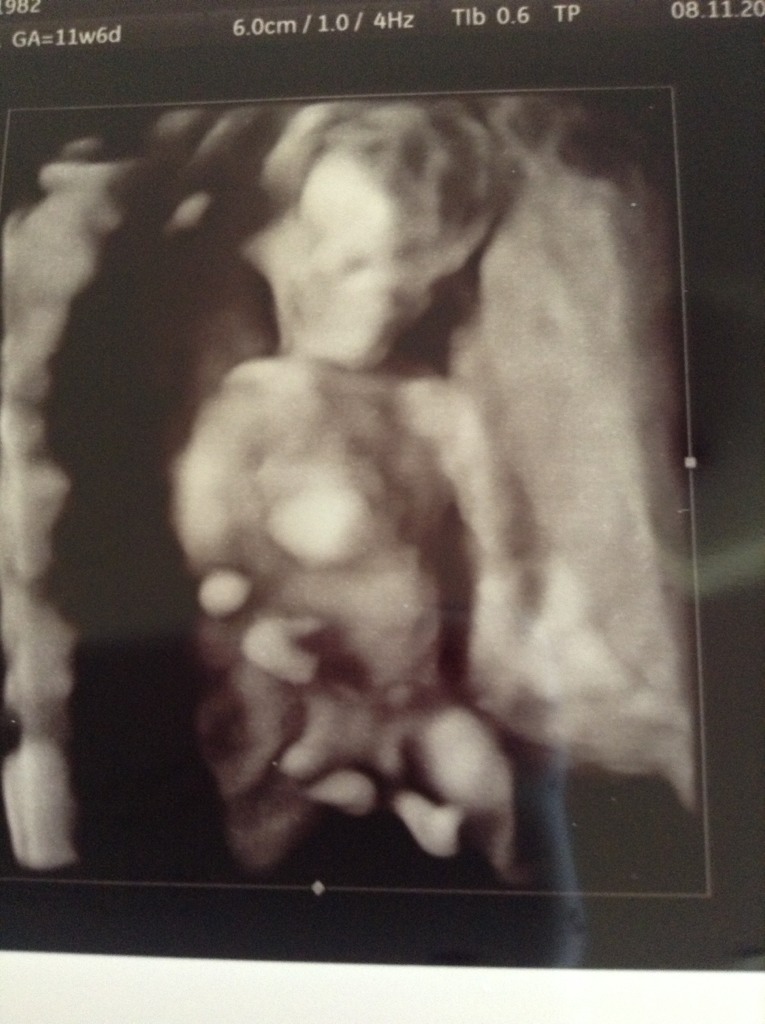

Hi girls, here is a pic that I think might be nub? The tech refused to give me any potty shots or nub shots but I think this one might show it?

Have a couple more and will post later but I think this is the clearest. Would love to know your guesses please :)